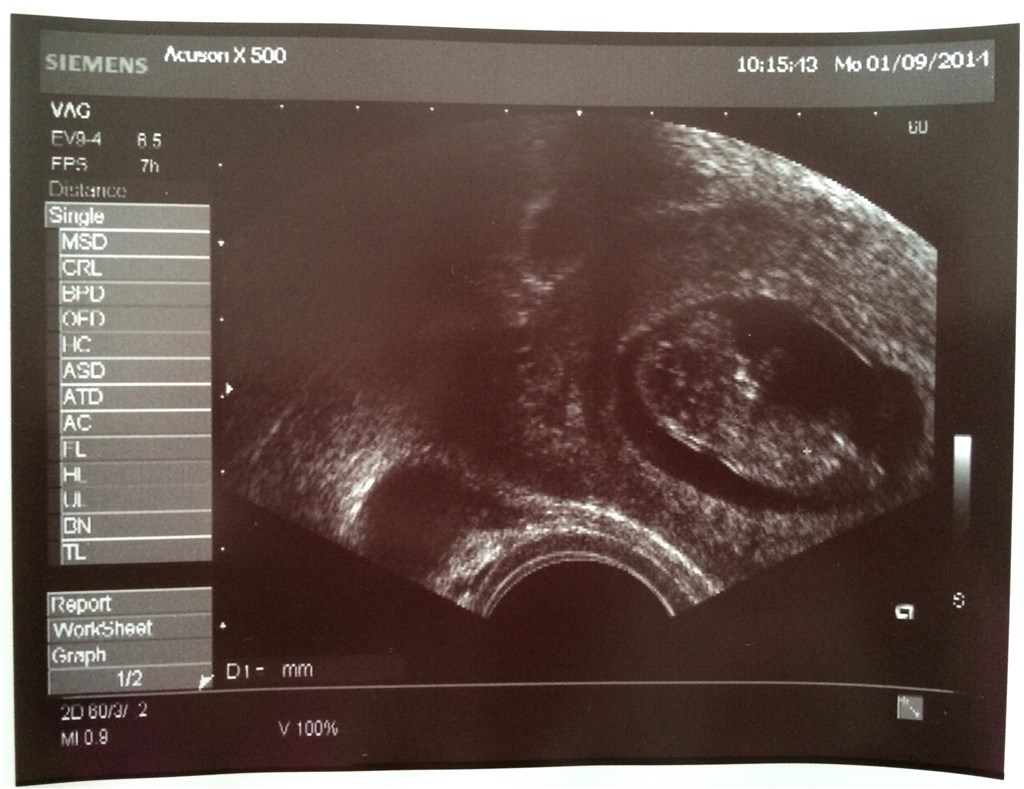

jeg har desværre ik noget scannings billed endnu. men overvejer og tage til scanning i morgen hvor jeg også ville være de der 10 uger..

men jeg er nys omkring hvor meget man kunne se og om den lille bevægede sig ?

Man kunne se arme, ben, krop og hoved og til tider navlestreng og selvfølgelig et lille hjerte blinke.

Den bevægede sig ikke rundt, men hun sagde at det kunne være at om 5 min så lå den slet ikke stille -men hun var glad for at den lå stille ellers kunne hun ikke måle :-)